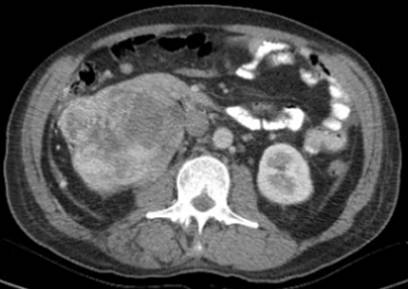

La tomografía simple y contrastada revela trombo tumoral a nivel auricular derecho, con extensión al ostium de la vena renal derecha (figura 1), sin presencia de lesiones metastásica pulmonares, ni hepáticas, sin ectasia de la vía biliar, revela además la presencia de un tumor renal derecho de 15 cm, con 15 UH en fase simple y 59 UH en fase arterial (figuras 2, 3 y 4). El ecocardiograma transesofágico demostró presencia de trombo tumoral en aurícula derecha del 95% de la luz de ésta (figura 5).

Figura 2 Tomografía simple y contrastada que demuestra defecto de llenado a nivel auricular, trombo a nivel de la vena cava inferior, vena renal y tumor renal derecho.

Con los estudios de extensión se establece el diagnóstico de tumor renal derecho cT3c N0 M0, con trombo tumoral Neves IV, así como síndrome de Stauffer. El paciente recibió valoración por medicina interna debido a la hiperglucemia, hiponatremia e hiperazoemia; manejado medicamente con insulina ultrarapida y basal, además con reposición hidroelectrolítica. Se decide someter a tratamiento quirúrgico, el cual consistió en la realización de una nefrectomía radical derecha, resección de trombo de la vena cava inferior a través de venotomía, con abordaje de tipo Chevron y resección intracavitaria de trombo auricular mediante atriotomía a través de esternotomía y by pass cardiopulmonar (figuras 6 y 7). Presentó un sangrado transoperatorio de 2000 ml, requirió trasfusión de 10 concentrados eritrocitarios, 4 plasmas frescos congelados y 4 aféresis plaquetarias, con un tiempo de bomba de circulación extracorpórea de 1 hora y 20 minutos.